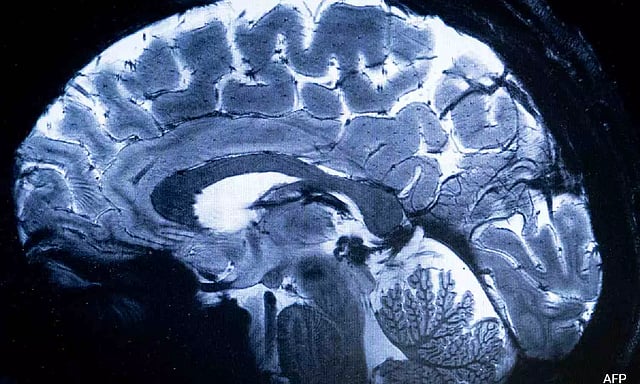

The magnetic field created by the scanner is a whopping 11.7 teslas (AFP)

SACLAY [France]: The world's most powerful MRI scanner has delivered its first images of human brains, reaching a new level of precision that is hoped will shed more light on our mysterious minds -- and the illnesses that haunt them.

The magnetic field created by the scanner is a whopping 11.7 teslas, a unit of measurement named after inventor Nikola Tesla.

This power allows the machine to scan images with 10 times more precision than the MRIs commonly used in hospitals, whose power does not normally exceed three teslas.

On a computer screen, Vignaud compared images taken by this mighty scanner, dubbed Iseult, with those from a normal MRI.

"With this machine, we can see the tiny vessels which feed the cerebral cortex, or details of the cerebellum which were almost invisible until now," he said.